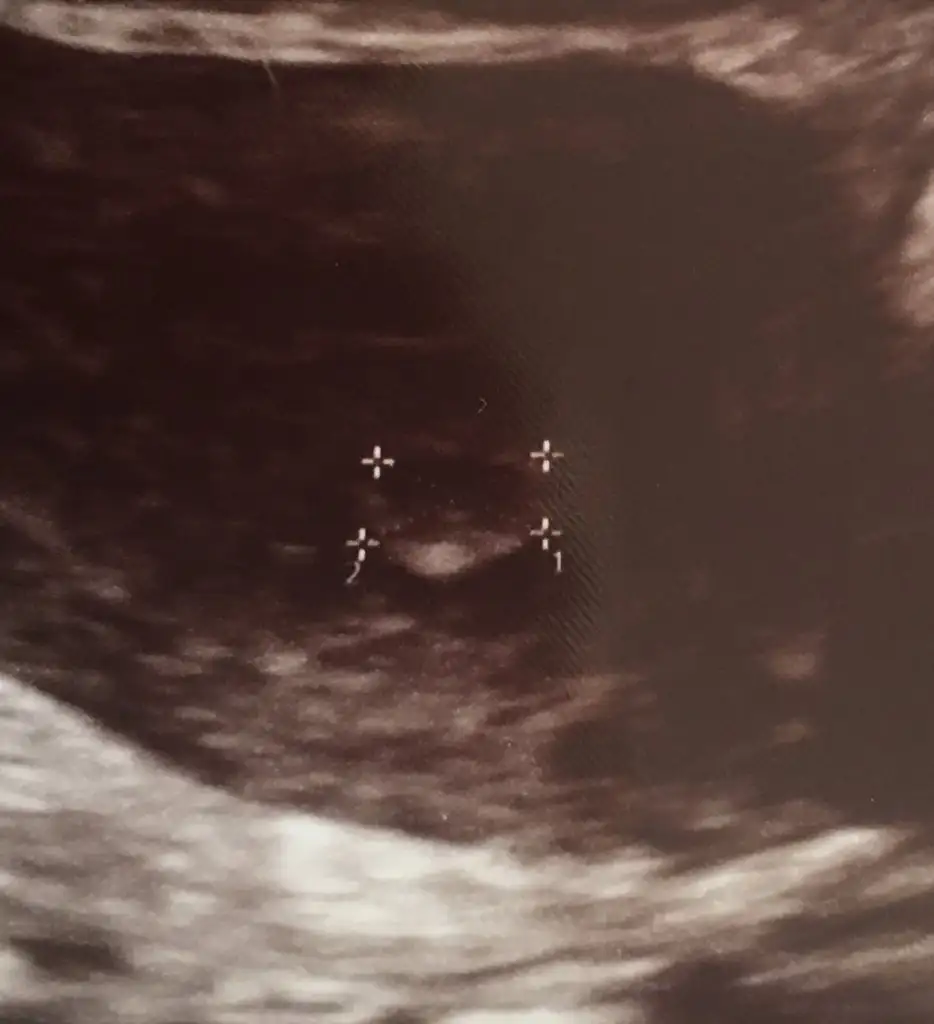

Aynen bende senin gibiyim canım ilk bebe olcak inşlh kaç haftalıkdınKızlar keseyi gördüm bugün ama yolk kesesi hakkınca birşey söylemedi kenardaki beyazımsı şey mi oluyor acaba? İlk hamileliğim bu arada tecrübesizim

Selam canım. Evet salı günü gördük keseyi :) sende durum ne :)canım gittin mi keseyi görmeye? :)

Ay bende napcagimi bilemedim, pazar memlekete gitmek icin yola cikcaz, yarin gitsem doktora keseyi gorurmuyum, yoksa memlekettemi doktora gitsem kararsizim.Selam canım. Evet salı günü gördük keseyi :) sende durum ne :)

Bence yola cikmadan git bir doktora için rahat etsin.Ay bende napcagimi bilemedim, pazar memlekete gitmek icin yola cikcaz, yarin gitsem doktora keseyi gorurmuyum, yoksa memlekettemi doktora gitsem kararsizim.